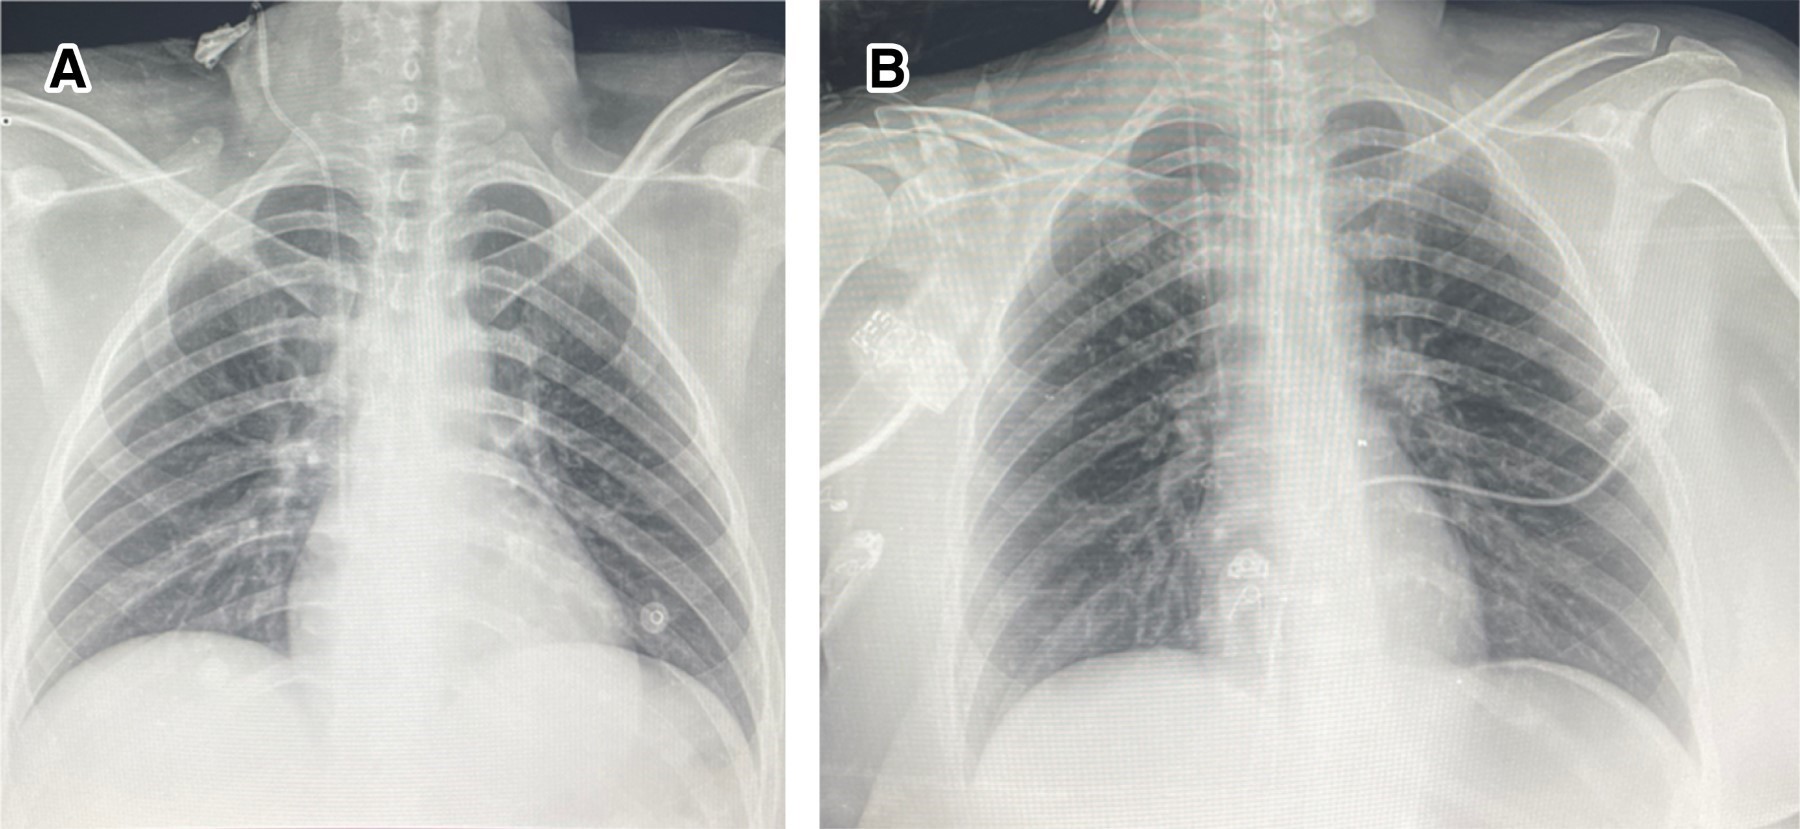

Evolución: durante su estancia la paciente se sobreinfectó con Candida glabrata y Pseudomonas aeruginosa, por lo que se le dejó manejo guiado por cultivos con voriconazol y ceftolozano/tazobactam a dosis habituales. La sedación inhalada se mantuvo en la paciente por un periodo de cuatro días a una dosis promedio entre 6 y 10 mL/h titulada con base en el BIS, posterior a los cuales la dosis del anestésico volátil se disminuyó de forma progresiva hasta su suspensión y continuó manejo a base de sedación convencional. La paciente persistió sólo con muy leves sibilancias espiratorias bilaterales, se realizaron dos extubaciones sin éxito, por lo que a los 15 días de intubación se decidió realizar traqueostomía, se egresó de la UCI a los 24 días de estancia con tienda traqueal a 5 L/min, saturando 98% y finalmente egresó de piso hospitalario (Medicina Interna) a los 44 días de estancia hospitalaria posterior al retiro de la traqueostomía y con cita de seguimiento por neumología, medicina física y rehabilitación. En la Figura 1 se pueden observar las radiografías de la paciente con la exacerbación asmática y después de la misma.

Figura 1